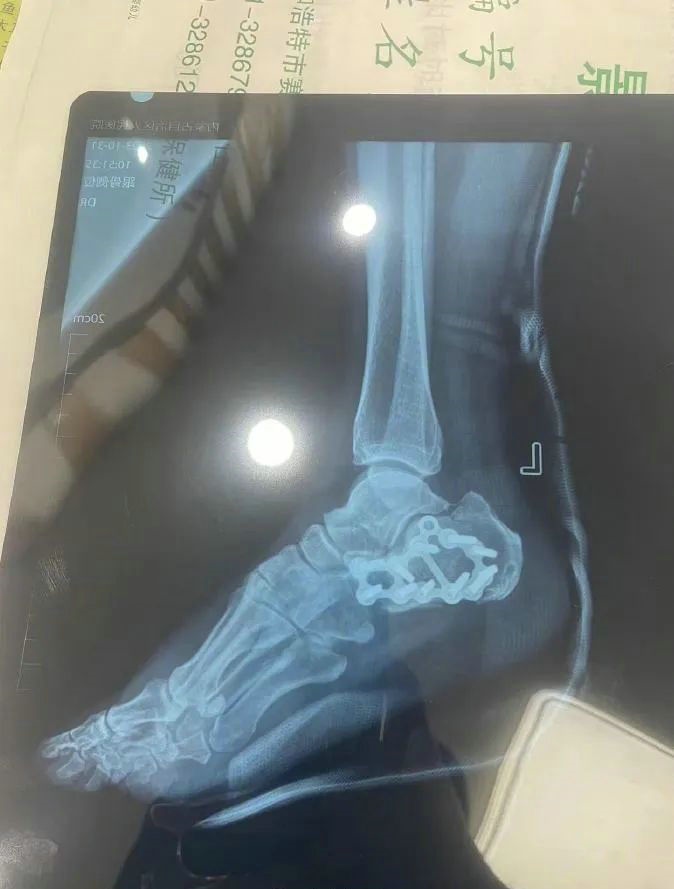

“那時(shí)候我剛工作了兩天,在第三天10月22日下午施工過(guò)程中從三層高的鐵架上摔了下來(lái),導(dǎo)致30厘米左右的鋼筋刺穿我的右側(cè)臀部,左腳跟也粉碎性骨折,被送往內(nèi)蒙古自治區(qū)人民醫(yī)院救治,當(dāng)晚做了手術(shù)取出刺在右臀部的鋼筋,10月30日又進(jìn)行了左腳粉碎性骨折手術(shù)?!崩紫壬嬖V記者。

據(jù)雷先生介紹,當(dāng)時(shí)內(nèi)蒙古騰龍建設(shè)工程有限公司許經(jīng)理問(wèn)過(guò)他賠付10萬(wàn)元能否解決問(wèn)題,他認(rèn)為這樣不太妥當(dāng)。“因?yàn)槲业淖竽_骨折還要進(jìn)行二次手術(shù),并且我臀部受傷不能坐著,只能包車(chē)回家,會(huì)產(chǎn)生一系列的費(fèi)用?!崩紫壬f(shuō)。